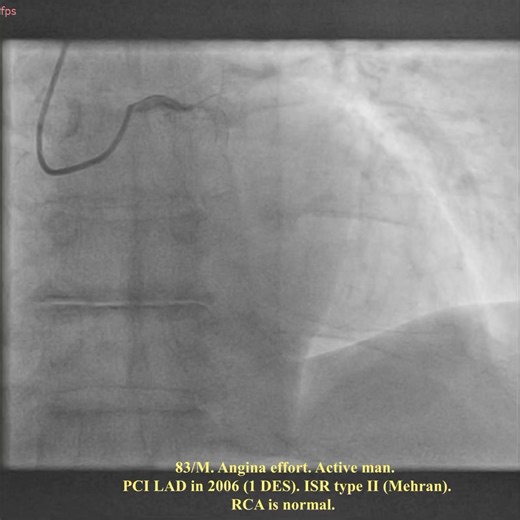

Aliyor Ganiev on Instagram: "🇬🇧 IVUS guided BioPCI in pt with ISR (19 y

…

576 views

3 months ago

Instagram

dr._aliyor